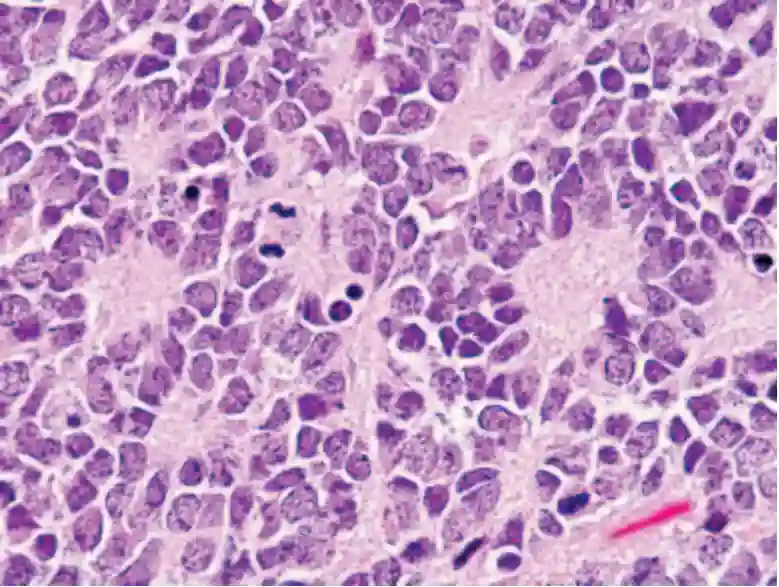

Multiple Homer-Wright Rosetten bei einem Patienten mit einem PNET. HE Färbung bei einer Vergrößerung von x400. Abbildung adaptiert von Wippold et al. 2006.